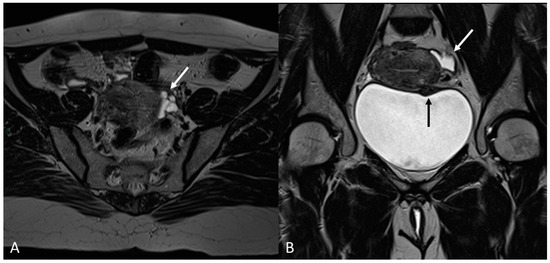

In this paragraph, we will explore the main signs in post-operative imaging in order to provide the radiologist with an indication to evaluate MRIs of women with extensive and complex endometriosis undergoing surgery (Figure 15 and Figure 16).

Figure 15.

Para-uterine fluid collection in a 43-year-old female who underwent several gynecological surgeries for deep infiltrative endometriosis. (A) Axial T2WI. Compartmentalized hyperintense collection in the left para-uterine area after pelvic surgery (white arrow). (B) Coronal T2WI. Endometriotic localization of the vescico-uterine pouch (black arrow).

Figure 16.

Localization of endometriosis in the left parametrium and ureteral stenosis in 49-year-old female who underwent supracervical hysterectomy, bilateral salpingectomy and mild vaginal bleeding and abdominal pain. (A) Axial T2WI; (B) Sagittal T2WI. Endometriotic localization of the left parametrium (white arrow), with irregular margins and heterogeneous signal intensity. Tractions towards the sigmoid colon, left pararectal fascia, anterior pelvic peritoneal reflection and adnexa. Ureteral stenosis caused by the parametrial plaque (dotted arrows in (B)). (C) Axial T2WI; (D) Axial fat-suppressed T1WI. Endometriotic nodule of the left pelvic wall (white arrow).